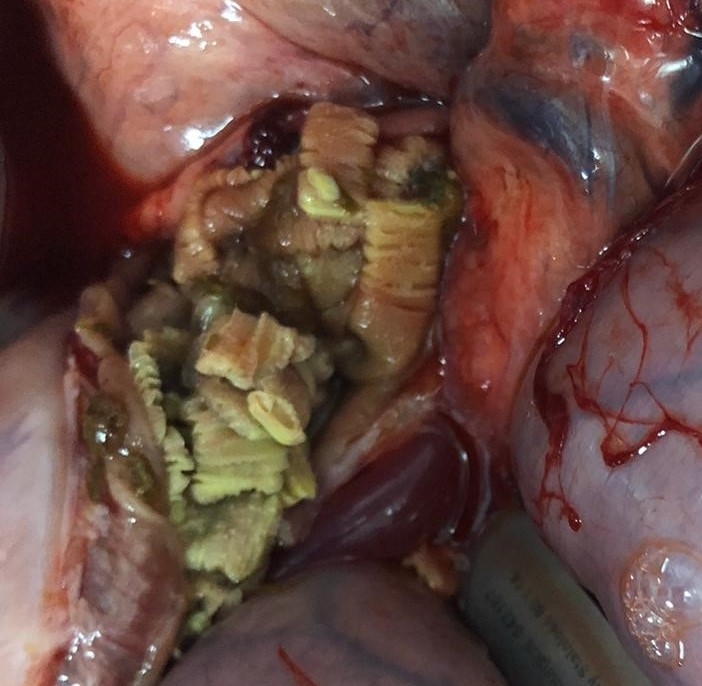

Live tapeworm infection discovered 4 days after receiving praziquantel tapeworm treatment

The individual colic cases occurred over several years (one in 2014, and three in 2019/2020) at a well-managed Thoroughbred stud farm. Two of the yearlings required euthanasia while two made a full recovery. Post mortem/laparotomy examinations of three yearlings revealed large live tapeworm infections, and three of the cases suffered ileocaecal intussusception; where a section of the intestine slides inside an adjacent section. This was despite the yearlings being treated with praziquantel (tapeworm treatment) at 6 and 12 months of age.

The most concerning finding was that two of the live tapeworm infections were discovered just days after the yearlings had received the praziquantel dose, therefore raising suspicions of praziquantel resistance (meaning the drug would no longer kill tapeworms).